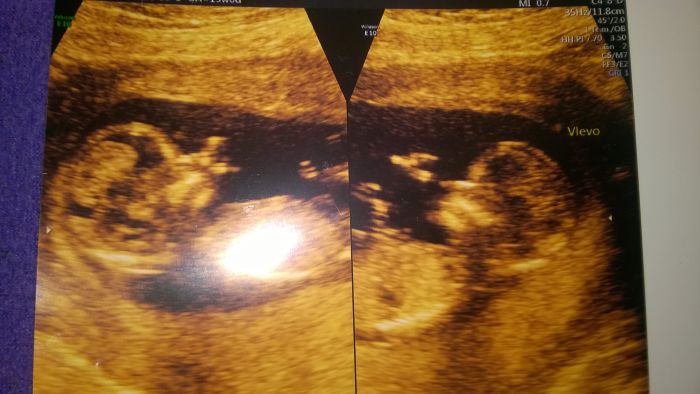

Ahojte,to s tou Janou bol aj pre mna sok.uprimne aj jsem ji litivala ale aj jsem si rikala,ze tak blba holka ani neni.. Jo jestli je nekdo zvedavy jak vypadaji na ultz dvojcatka, prikladam foto.. My stale nevime co budeme mit, tak jestli mate typy..